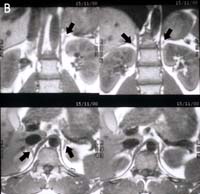

ต่อมหมวกไต เป็นอวัยวะคู่ซึ่งอยู่บริเวณส่วนบนของไตทั้งสองข้าง ต่อมหมวกไตข้างขวาจะอยู่เหนือกว่าและอยู่ด้านข้าง lateral ต่อไตมากกว่าข้างซ้ายซึ่งจะอยู่หลังกว่า splenic vessels และเห็นในระดับของ pancreatic tail ดังรูปที่10

รูปที่ 10 ภาพ CT และ MRI ของต่อมหมวกไตปกติ

รูป A. ภาพ CT ลูกศรแสดงต่อมหมวกไตปกติข้างขวาและข้างซ้าย ( ระนาบ coronal ) รูป B. ภาพ MRI T1 WI ของต่อมหมวกไตปกติข้างขวาและข้างซ้าย (ลูกศร) เป็นระนาบตัดขวาง

รูปร่างของต่อมหมวกไตอาจเปลี่ยนแปลงตามระดับของ cross sectional imaging ข้างขวามักเป็นรูป linear หรือ inverted V หรือ K configuration ข้างซ้ายอาจเป็น linear, inverted V, triangular, inverted Y หรือรูปดาว เป็นต้น ความกว้างของขาประมาณ 2-3 มิลลิเมตร และไม่ควรเกิน 5 มิลลิเมตร(11) ส่วนใหญ่ของ cortisol-producing adrenal masses จะใหญ่กว่า 2 เซนติเมตร ซึ่งเห็นได้ชัดใน CT หรือ MRI การตรวจโดย CT มักจะเป็นทางเลือกแรกซึ่งสามารถวินิจฉัยได้แม่นยำ เนื่องจากผู้ป่วยเหล่านี้มักอ้วนมีไขมันล้อมรอบต่อมหมวกไตมากทำให้เห็นได้ชัดเจน ใช้เวลาตรวจสั้นและราคาถูกกว่า MRI